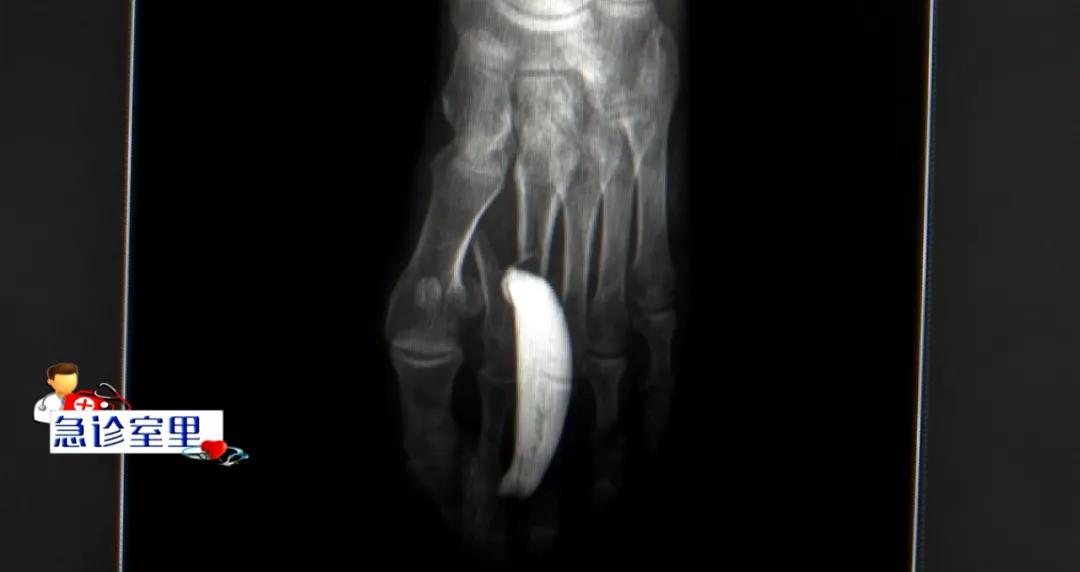

为了防止伤口感染和出血加重,急诊科医生立即进行了包扎,随后,李小军被推到了影像医学科做X光检查,结果显示,他的左脚跖骨骨折。骨科医生会诊后,建议李小军做急诊手术治疗,随后,他被转到了骨科做手术准备。